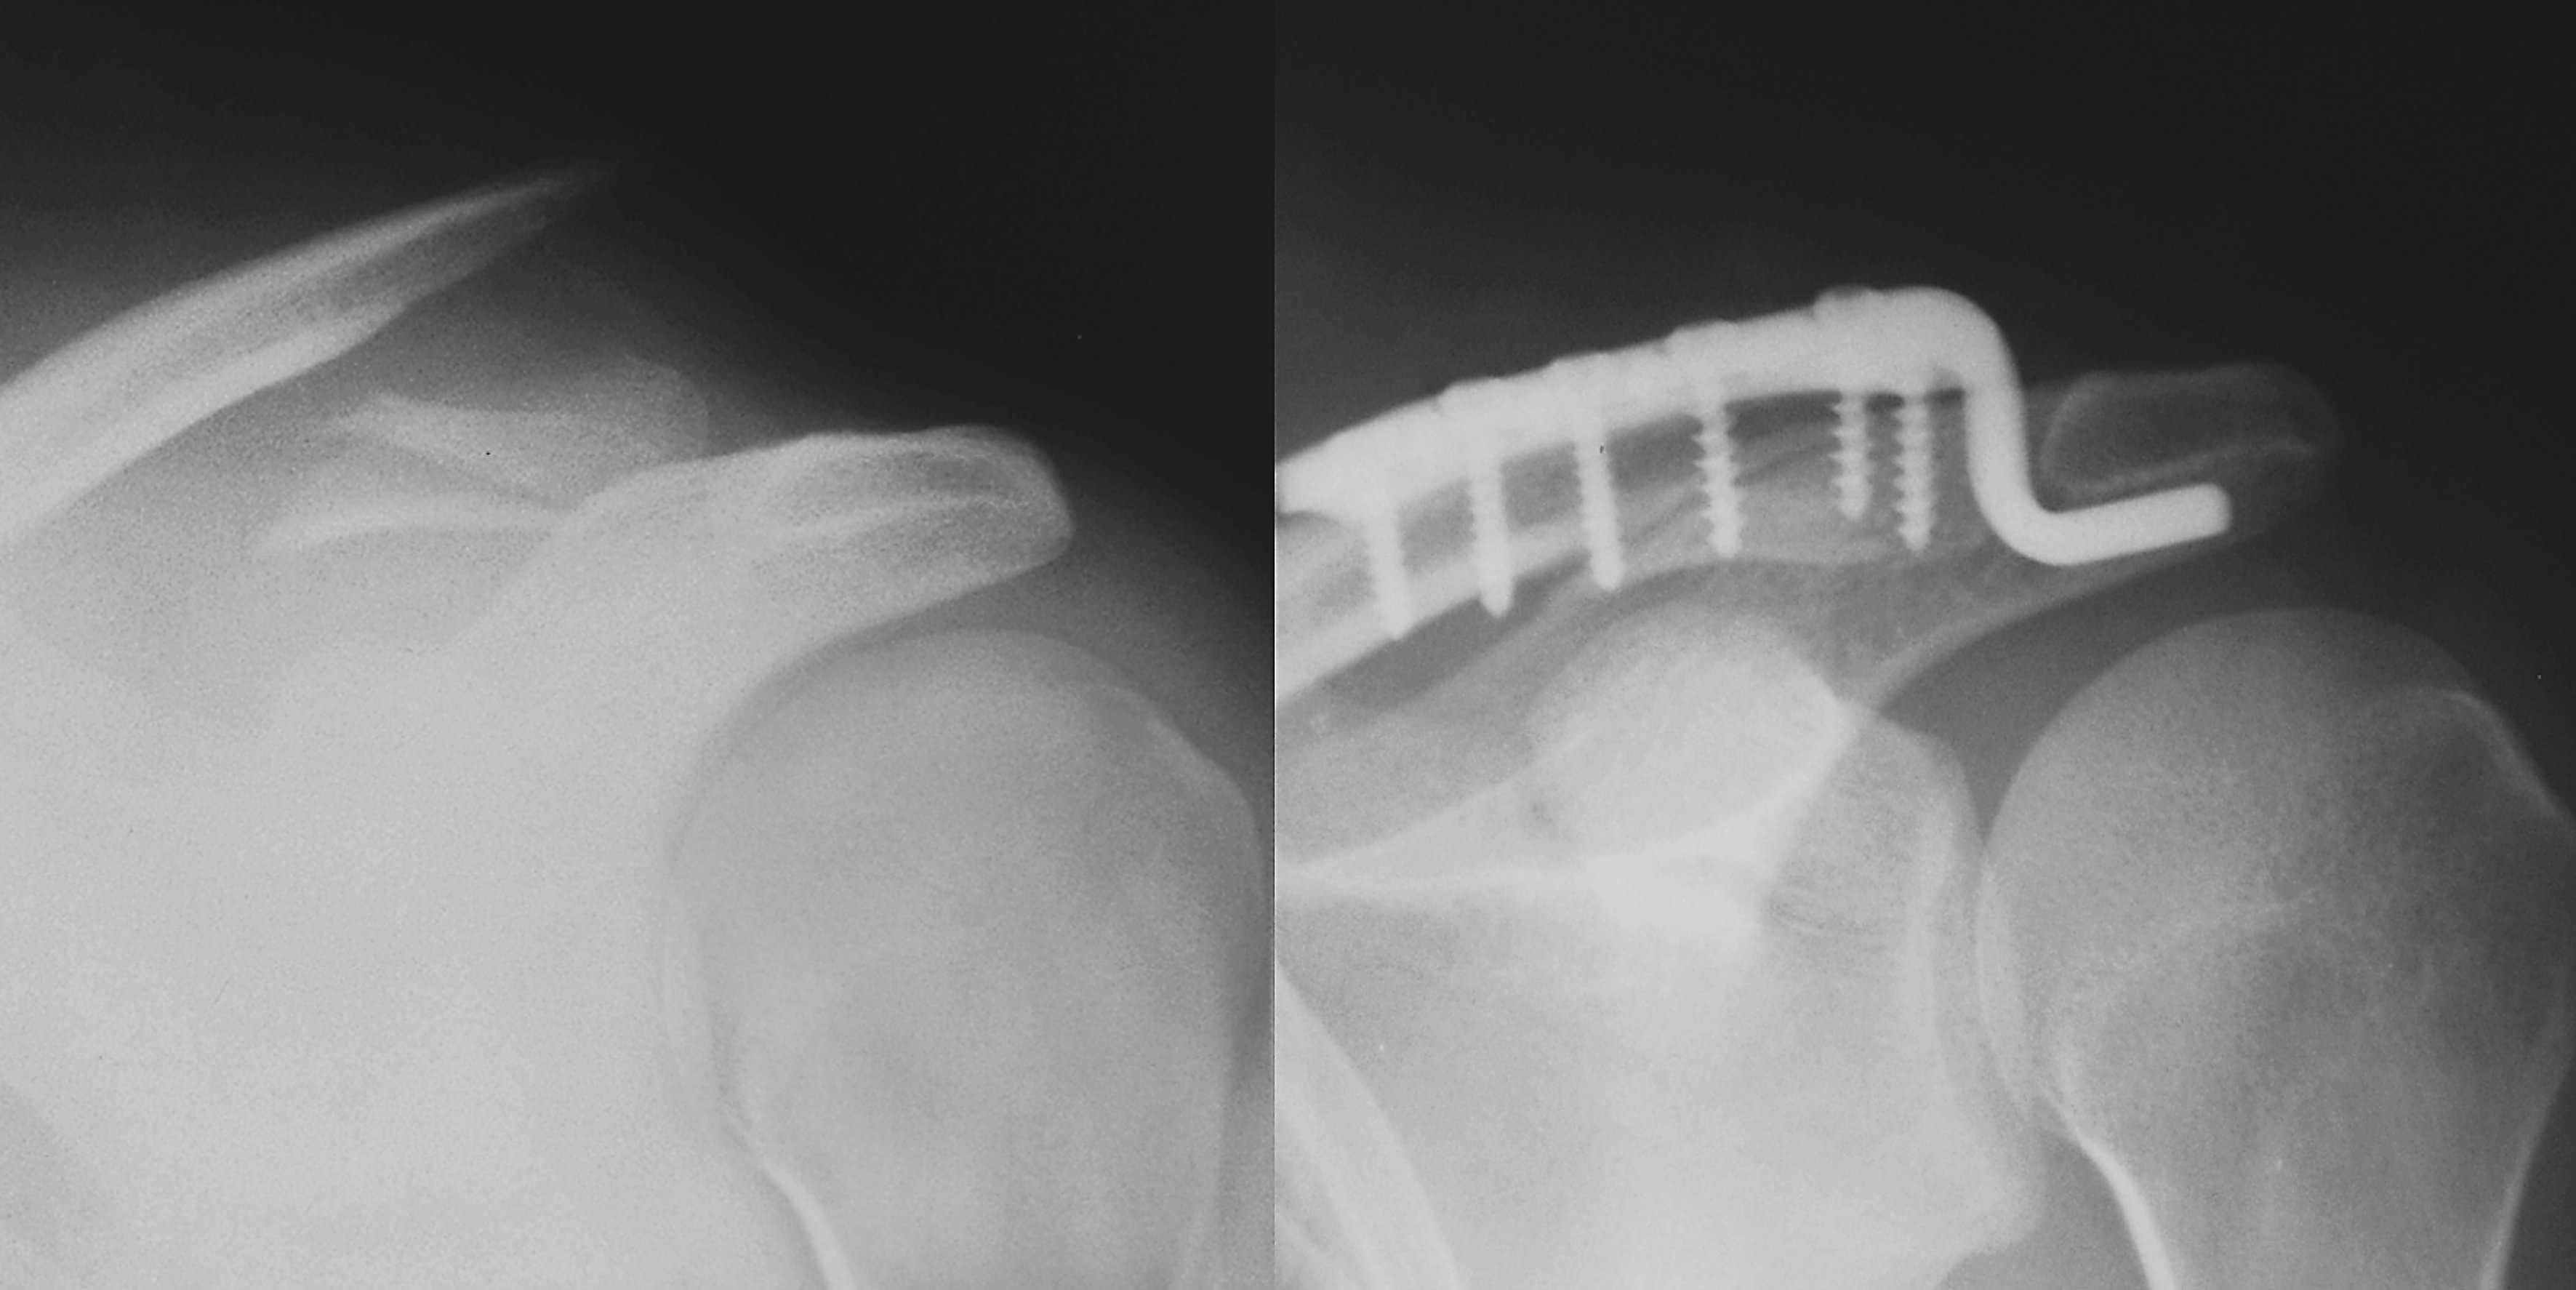

Вывихи и переломы ключицы презентация - 85 фото